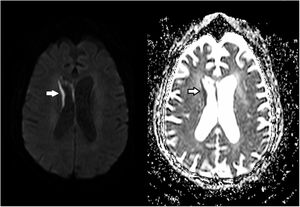

A 68-year-old woman with chronic bronchitis was admitted to the Intensive Care Unit at the start of the COVID-19 pandemic due to respiratory failure and bilateral lung infiltrates consistent with SARS-CoV-2 infection, though PCR testing proved negative on several occasions. During admission she suffered a progressive altered level of consciousness, requiring orotracheal intubation. Aspergillus lentulus was isolated from the bronchial aspirate. Lumbar puncture revealed: glucose 24 mg/dl, total proteins 133.6 mg/dl, leukocytes 136/µl and mononuclear cells > 95%. The brain CT scan showed no acute lesions and the brain MRI study revealed subependymal enhanced signal intensity around the frontal horn and atrioventricular zone of the lateral right ventricle (Figs. 1 and 2), with diffusion restriction in the apparent diffusion coefficient (ADC) study (Fig. 3). With the suspicion of fungal ventriculitis, PCR testing for Aspergillus spp. was performed in cerebrospinal fluid, with positive results.